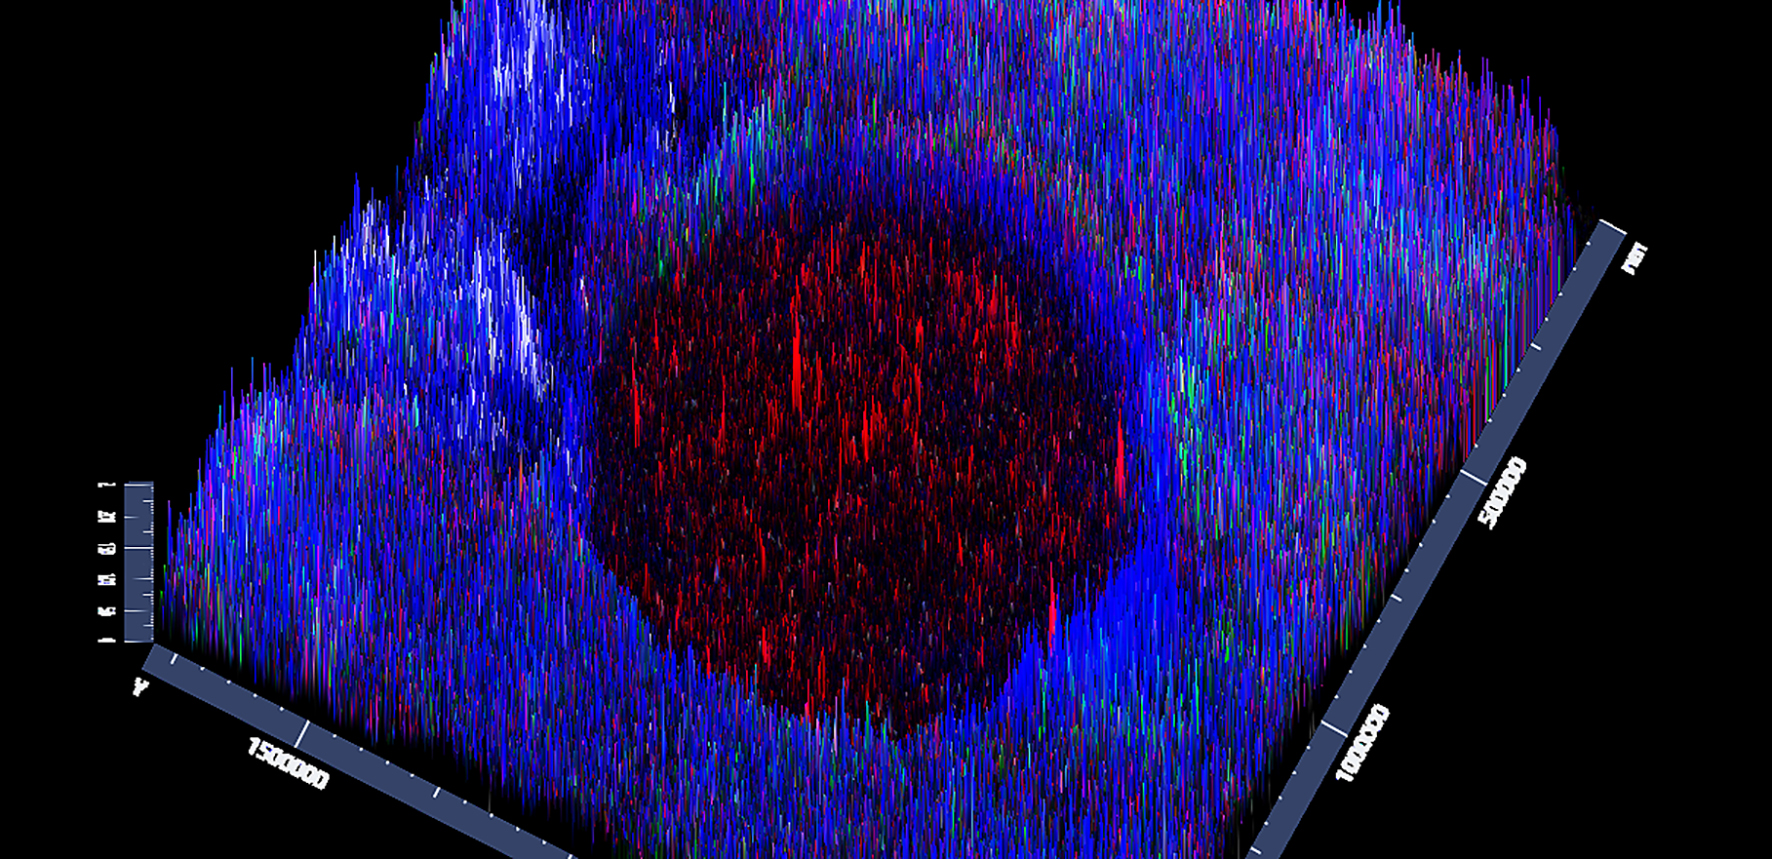

The image below shows Human HCC and IC – this is a top down view of the image above, and shows HCC cells (red) engrafted “entering” a human PCLS, nuclei (blue), with added immune cells (green).